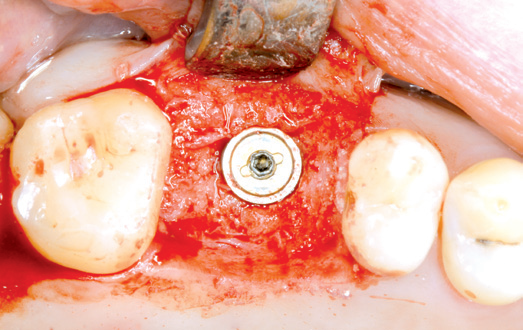

04/10 - Preparation of the implant bed for internal sinus lift with bone condensorInternal sinus lift with maxresorb® inject - case Dr. Frank Kistler

09/10 - Inserted implant before wound closureInternal sinus lift with maxresorb® inject - case Dr. Frank Kistler